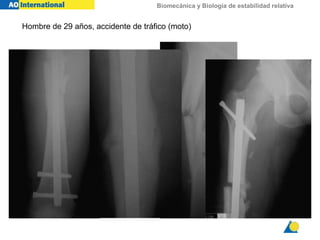

Hombre de 29 años, accidente de tráfico (moto)

Biomecánica y Biologíade estabilidad relativa Hombre de 29 años, accidente de tráfico (moto)